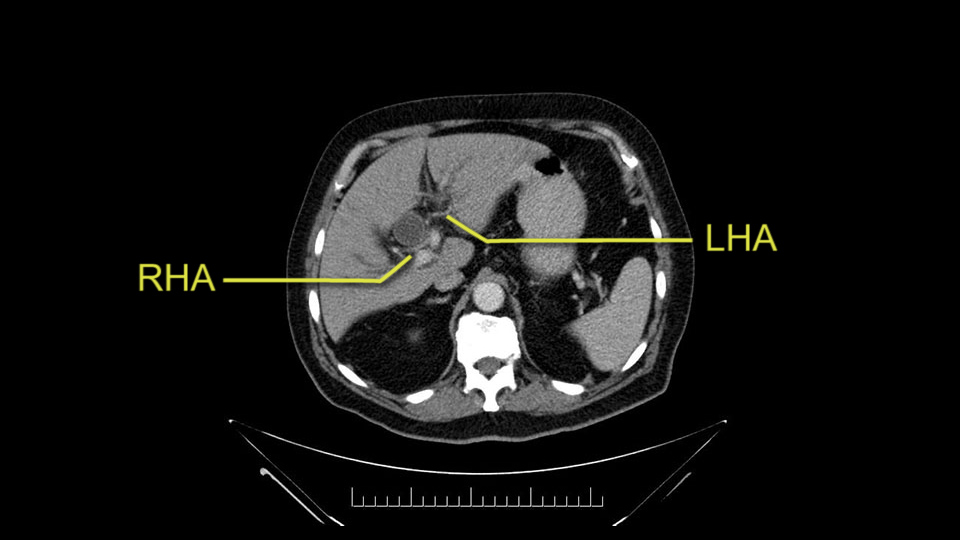

He has normal arterial anatomy: no accessory or replaced right hepatic artery, which is important because sometimes the right hepatic artery can come behind the neck of the pancreas and you have to be careful of that in a Whipple dissection.

Then you look for anomalies. The one you worry about the most doing a Whipple is a replaced or aberrant right hepatic artery coming off the SMA at its origin. So again, find the SMA. You can find it because the renal vein goes through it. Follow it up, up-up-up. Nothing coming off of there that I can see here. Nothing coming off of it, nothing coming off of it and just to confirm it, look at the celiac trfurcation. There’s the celiac, there’s the bifurcation, there's the splenic artery, hepatic artery. Make sure there’s a right, which there is here. The right usually goes under the bile duct: important when you’re going around the bile duct to do a Whipple. A replaced right goes under the portal vein and the bile duct way over here on the right. That’s about it.

The other slowing down moment would be the gastroduodenal artery. Confirming that the gastroduodenal artery is not a dominant artery supplying blood to the liver. Liver failure is something which we don’t want due to altered blood supply to the liver or hampered arterial blood supply to the liver. So I would dissect out the hepatic artery, the left and right branches very clearly. Put a bulldog clamp on the gastroduodenal artery, make sure that the perfusion of the liver is excellent on the right and left side, and then divide the gastroduodenal artery. I would avoid using crushing instruments or crushing clamps on the gastroduodenal artery because they have a tendency to shatter in patients who are old with friable vessels so you have to be careful and tackle it with the help of a 5-0 or a 6-0 prolene sutures. In younger patients, I would just apply clips and move on when it comes to dividing the gastroduodenal artery.

To plan a pancreatoduodenectomy, we start by reviewing the vascular anatomy, especially the origin of the celiac trunk, here, in front of the aorta, looking for any evidence of stenosis. In addition, we look at the origin of the superior mesenteric artery, to look for any branches, and any replaced right hepatic arteries coming from the superior mesenteric artery; which does occur in about 12% of the population.

The second point about the vascular anatomy-, is to again look for right hepatic arteries in the hilum, coming from the superior mesenteric artery by palpating-through the Winslow Hiatus. Usually we will check for a pulse in the posterior aspect of the hepatic hilum, where a right hepatic artery should not usually be found. In this case, the precaution is to avoid an accidental ligation of the right hepatic artery that might jeopardize perfusion of the right lobe, or if there is a completely replaced hepatic artery that can put the liver circulation at risk.

E l segundo punto de la anatomía vascular, es nuevamente buscar arterias hepáticas derechas, en el hilio, provenientes de la mesentérica superior y eso lo hacemos palpando -a través del Hiato de Winslow- el hilio hepático y usualmente sentiremos un pulso en el aspecto posterior del hilio hepático, donde no debe ir el recorrido usual de la rama derecha de la arteria hepática. En este caso, la precaución es no realizar una ligadura accidental de la arteria hepática derecha y poner en riesgo -posiblemente- la perfusión del lóbulo derecho, o aún esta arteria puede reemplazar completamente la arteria hepática y poner en riesgo la circulación del hígado.

I am a believer in pylorus preservation. And in this case I see no reason why that wouldn't be possible. Mobilize the duodenum, divide the gastroepiploic vessels and divide the duodenum. I try to divide it with a linear stapler about four centimeters from the pylorus to have adequate length for my GI anastomosis. This facilitates exposure of the head neck of the pancreas. I find the gastroduodenal artery. This patient has normal arterial anatomy. Always on every preoperative CT scan I look to see if there is a replaced right hepatic. In this case I did not see one. Regardless of how confident I am I always look carefully for variant anatomy. I always do a clamp test on the GDA before ligation. I doubly ligate the GDA with not just a tie but a suture ligature because of the risk of GDA blowout in patients with a leak.